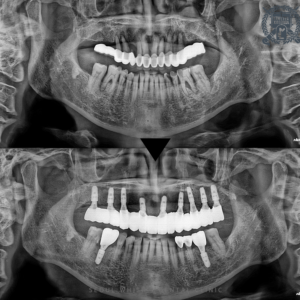

광복동치과, 소홀했던 치주질환 임플란트로 기능회복!

광복동치과, 소홀했던 치주질환 임플란트로 기능회복! 안녕하세요. 광복동치과 서울화이트S치과 입니다. 최근 몇 년동안 19세 이상 성인의 병원 외래 질환에서 치주질환이 1,2위를 차지할 만큼 치주질환으로 불편함을 호소하시는 분들이 많이 계십니다.…